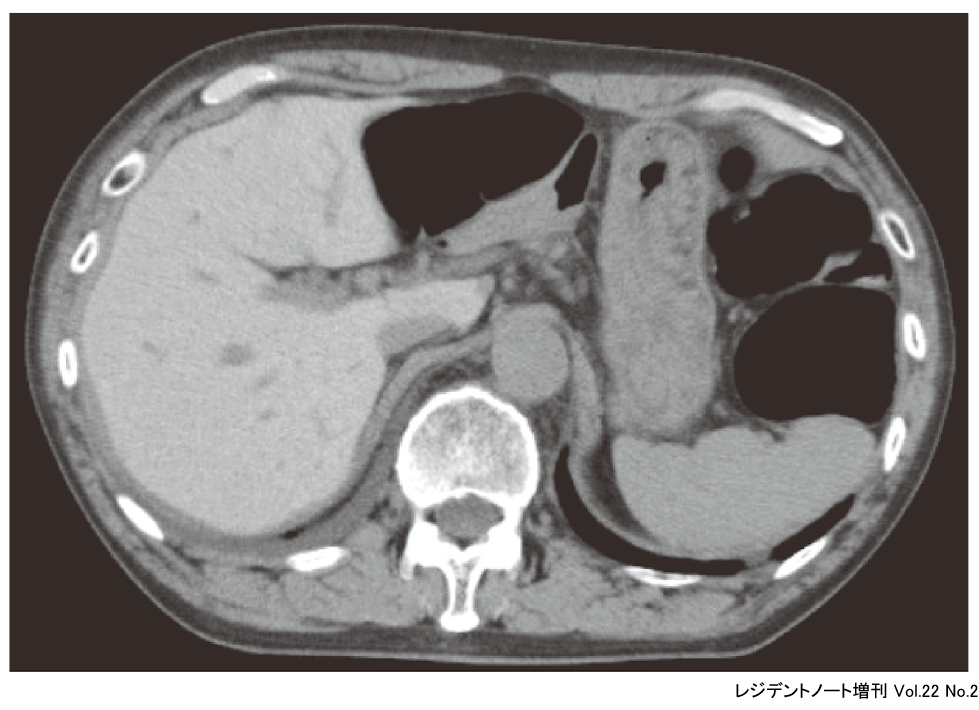

単純CTで肝実質がびまん性に高吸収に描出されている.肝実質と門脈(図1▶︎),IVC(inferior vena cava:下大静脈,図1︎▶)とのコントラストが増強しており,脾臓(図1︎ S)と比較しても肝実質が高吸収になっていることがわかる.びまん性に濃度変化を生じていると,一目では変化に気がつかないことがある.比較画像がある場合はその画像との対比を,比較画像がない場合には周囲にある構造と濃度を比較することで,変化や異常に気がつきやすくなる.今回の場合では,肝実質と肝内血管の濃度差,肝実質と脾臓の濃度差に気がつけるかどうかが最大のポイントとなる.